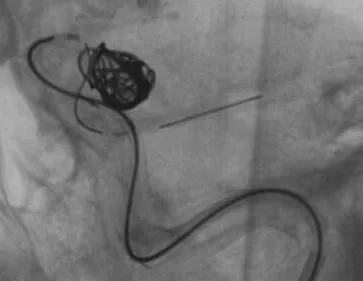

继续填塞,后面就简单了。最后的结果,一共用了四枚弹簧圈,栓塞致密,瘤体及破口都不显影了

顺利完成手术。几点体会:1、支架要选用Enterprise或LVIS jr,好定位。2、支架末端够用就行,不能留得太长。3、弹簧圈不要先解脱,支架释放成功再解脱,一旦失败还有余地。4、推导管的时候要拽着支架推送杆,不要让支架提前意外解脱了。5、颈内动脉瘤颈以远太细或有狭窄的不建议。6、缺点是技术稍显复杂,优点是能很好的将瘤颈填致密,难度不大,适合的病例可以选择。在此感谢各位长期指导我的教授及专家。感谢冯雷教授的经验分享。